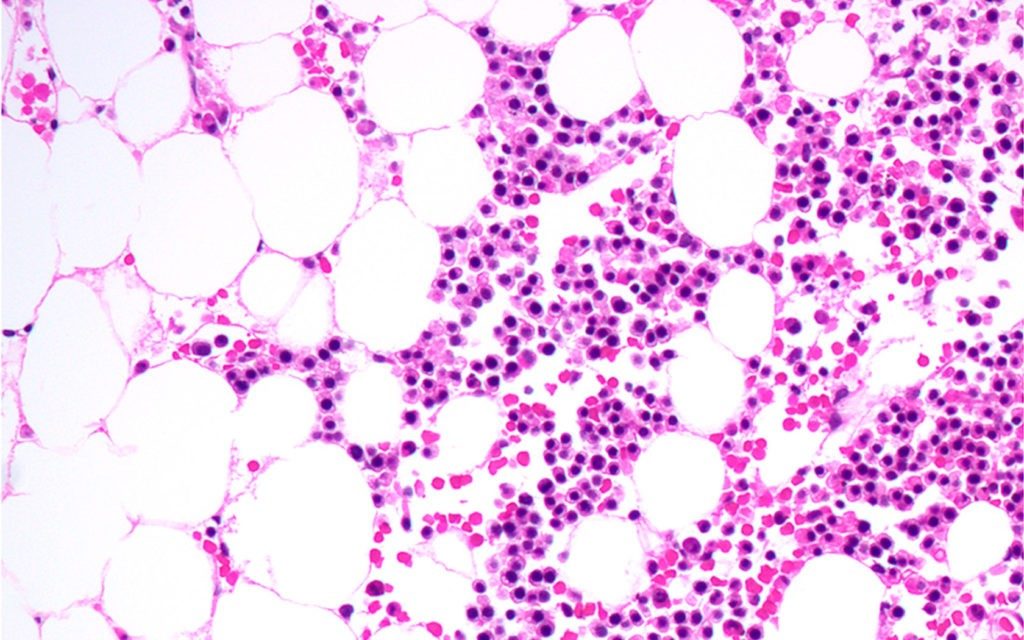

AML study reports high response rates with combination targeted therapy

Initial findings from a multi-national open-label phase Ib study of inhibitory drug therapy for relapsed or refractory acute myeloid leukemia (AML) have demonstrated a complete response in up to 50 percent patients say researchers at The University of Texas MD Anderson Cancer Center .

The patients, age 60 years or older, received therapy with venetoclax in combination with cobimetinib or idasanutlin. The clinical trial followed...